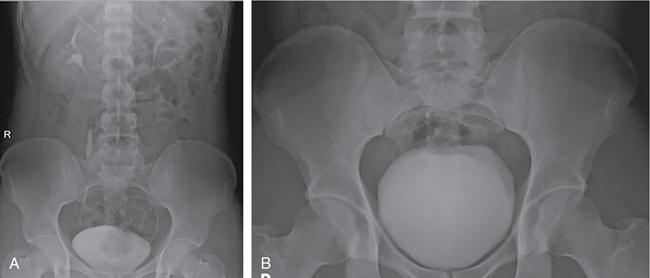

Roma Rai, Namita Singh The imaging techniques employed in an adult’s urinary system are vast with varied guidelines and algorithms. With the advent of multitude of newer imaging modalities, the strategies have constantly evolved. Non-contrast studies are still one of the strong pillars of imaging in general. However, contrast studies are an inescapable clinical necessity in majority of the cases and their usage is on a constant rise. It is therefore imperative to understand the concepts of contrast-induced nephropathy (CIN), which remains the most important possible unfavourable outcome, calling for a prudent usage of contrast. There are an array of risk factors which make a patient susceptible to the development of CIN. These risk factors are a history of diabetes mellitus, hypertension or other cardiovascular diseases, solitary kidney, renal transplant, age more than 50 years, pre-existing renal impairment, chronic infections like HIV and a patient on chemotherapy. If none of these risk factors are present, a contrast study can be performed without performing a serum creatinine. However, in presence of one or more of the risk factors, a serum creatinine followed by an estimated glomerular filtration rate (eGFR) is calculated. The patients are then stratified as very low-risk, low-risk and moderate-risk cases, using the eGFR values. In patients with eGFR of less than 60 mL/min, it is advised to consider alternative imaging modality. However, if the clinical benefits outweigh the risk of CIN, the procedure is done with precautions like withholding nephrotoxic drugs and adequate intravenous and oral hydration (pre- and post-procedure). The contrast dosage and concentration should be limited only to such an extent that the imaging quality is not compromised. The kidney ureter bladder (KUB) radiograph is the standard antero-posterior technique. The imaging is done in suspected cases of renal/ureteric colic for initial diagnosis or as a baseline for follow-up. The radiograph may rarely pick up other findings like gas in the urinary tract (emphysematous infections) or lytic bony metastases in renal cell carcinomas (Fig. 10.1.1). IVU, although replaced by CT urography in most of the centres, still remains one of the key urinary tract imaging techniques in centres having limited access to CT. IVU can be performed broadly in two ways using either the bolus infusion or the drip infusion method (Fig. 10.1.2). Bolus infusion: It is the technique widely used and it achieves better contrast opacification. The standard procedure involves patient’s preparation as that of a conventional radiograph along with a detailed history to rule out any contraindication to the contrast media in the form of a past history of allergic/anaphylactic reaction or in diabetic patients on metformin. Metformin should be discontinued in a patient for 48 hours prior to the examination. Contraindication to abdominal compression: A history of recent abdominal imaging, pain abdomen, abdominal trauma, suspicious obstruction on 5-min images or in post-renal transplant cases may lead to aggravation of the clinical condition or cause complications like urinary extravasation. Recent Advances: Digital tomosynthesis, a technique widely used in mammography, has been shown to considerably improve the adequacy of IVU. The technique is done using a standard X-ray tube and a digital flat panel detector. The tube head is rotated through an angle of 40 degrees in a horizontal direction for acquiring a set of images. The set of images acquired can be processed using different slice intervals. The literature has reported an improvement in overall adequacy to 95.5% from 46.5%, with the combined technique being pitched against computed tomography as an economically more viable option. However, the radiation dosage administered is more than the low-dosage CT technique employed in urinary calculi imaging (∼3.9 mSv). – Additional oblique views to confirm the location of visualized pathology/stone 1–3 min Delayed images till 24 hours if there is nonvisualization. ‘Rule of 6’: If there is nonvisualization of contrast in calyceal system, next film is taken after 6× interval between previous film and time of contrast given 5 min Abdominal compression applied post this acquisition 10 min (post-compression for 5 min) Collimated to kidneys Skipped in various institutions. KUB view may be added 15 min (immediately after releasing compression) Compression is not utilized routinely in many institutions Fluoroscopic visualization of contrast’s passage into the ureter followed by acquisition of the spot images Prone or supine images (gravity assisted) for opacifying post-obstructed segments Delayed images may be needed Towards the end of the procedure Oblique images for ureterovesical junction or post-void images for filling defects 98% sensitivity and 97% specificity in detecting calculous disease A non-contrast CT is adequate for calculous disease It is the imaging technique of choice in evaluating renal and urothelial malignancies Non-contrast CT can be performed even in emergency setting without any preparation Helps in detecting other possible causes of pain abdomen, e.g., appendicitis, diverticulitis, etc. Fastest technique available Provides detailed information Costlier and facility may not be available at some places Relatively less sensitive in picking up early calyceal changes Low-dose NCCT ~3 mSv Three-phase CTU-25–35 mSv Iterative reconstruction techniques have shown to reduce the dosage by half Retrograde ureterography is the technique of instilling contrast directly into the ureters by placing a catheter through bladder. The technique is seldom performed now with advent of cross-sectional imaging. It may theoretically be used as a second line of imaging to further characterise a ureteric lesion or as a primary modality in a suspected urothelial lesion having contraindication to intravenous contrast study. The practical applications are far too few in today’s imaging era. Conventional contrast techniques namely retrograde urethrography (RGU) and micturating urethrography (MCU) remains the initial imaging technique for urethra. MCU is also known as voiding cystourethrography. It is a routine to combine RGU and MCU for a comprehensive examination of urethra. Cross-sectional imaging is used for evaluating periurethral anatomy and pathology (Table 10.1.3). Ultrasound has been utilized for assessing thickness and length of urethral strictures and assessment of condition like spongiofibrosis by instilling saline.